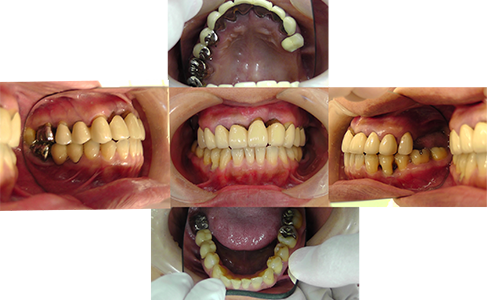

重度の歯周病に罹患していらっしゃいました。

被せ物もお口の状態と合っていなかったため、歯周病治療と補綴物の修復が必要です。

まずは、歯石をとるために丁寧にスケーリングを行います。

歯周病が初期段階の場合は、このスケーリングで完治することもございます。

重度の歯周病に罹っていたため、歯周外科治療を行いました。

歯肉を切開し、深い部分に残っている歯石を取り除きます。

新しい補綴物が完成するまで仮歯をつけてお過ごしいただきます。

製作した補綴物を装着します。

この患者さんはバリアソフトという補綴物を選択されました。

患者さんにとって扱いやすく、メインテナンスも簡単に行うことができます。

価格も抑えてお作りするこ とが可能です。